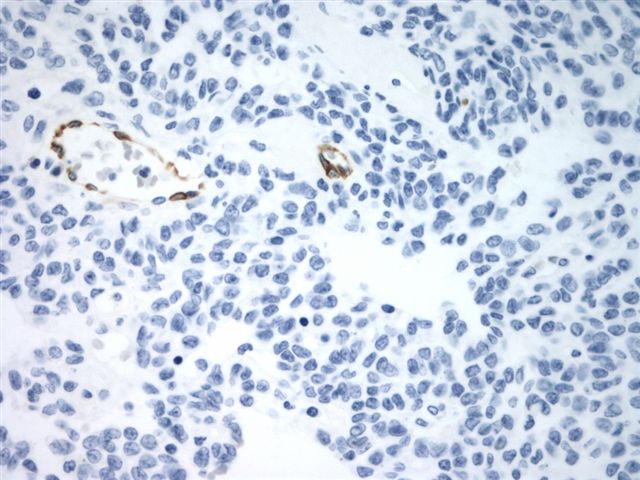

Microscopic (histologic) images

Contributed by Shabnam Zarei, M.D. and Sharon Bihlmeyer, M.D.

AFIP images

- CD99: 70% (Histopathology 1995;27:388, Mod Pathol 1998;11:769)

- Vimentin, WT1, CD56 and SMA